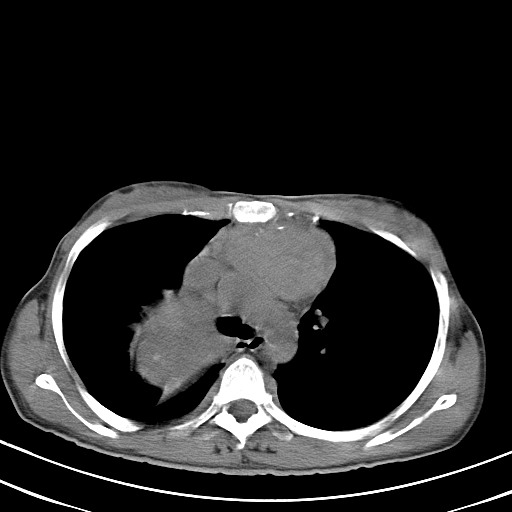

以下是引用汪涛同志在2007-8-2 0:40:00的发言:[br]病变虽然广泛,同时侵及双侧纵隔,但是无论左侧和右侧上下观察都是与右侧颈部甲状腺相延续的,而且强化幅度基本一致,又同时具有恶性病变病变的某些特征:肿块过大且密度不均,部分层面与正常纵隔结构分界不清,结合病史已有两年,考虑:胸内甲状腺肿恶变可能。[br]